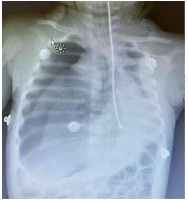

Durante a intercorrência, um interno aparece com uma radiografia de tórax do paciente que havia sido realizada à admissão.

enunciado 540552-1

Dada a condição atual do paciente e a conduta adequadas, assinale a alternativa correta.